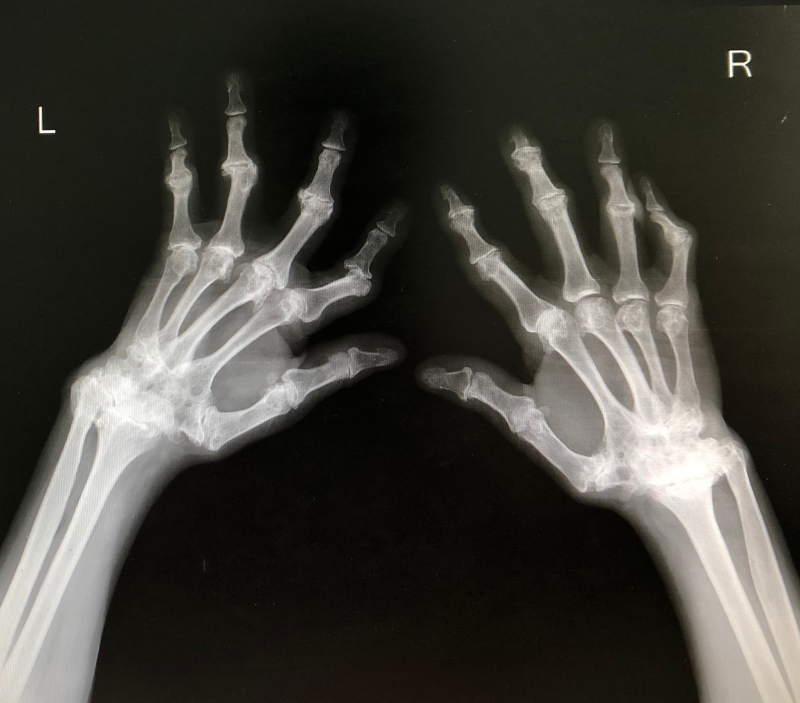

The goal of imaging the joints in patients with suspected rheumatoid arthritis is to rule out septic arthritis, identify soft tissue swelling, and discover early erosions of the joints. Radiography is inexpensive and provides for serial comparison of disease progression (Tsou, 2022). Percutaneous ultrasonography-guided aspiration may help localize and obtain samples of any fluid that can be found.

Image 1: Bilateral hand x-ray of a patient with Rheumatoid Arthritis.